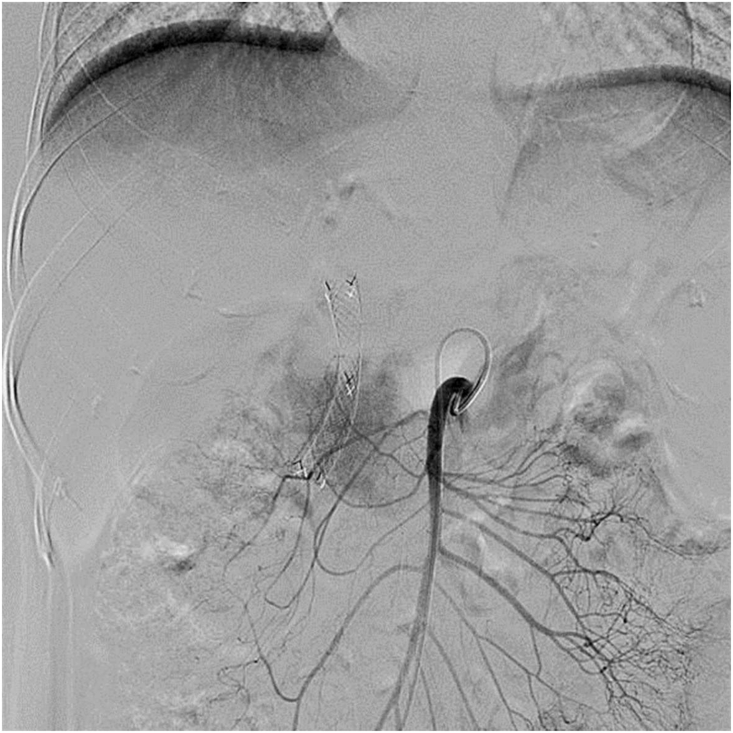

All TAI procedures were considered successful (total 85 times), withan average of 4.25 ± 1.55 procedures per patient. The treatment regimen involved 3 procedures in 10 cases, 4 procedures in 2 cases, 5 procedures in 2 cases, 7 procedures in 1 case and 8 procedures in 1 case. Five of the nine patients who did not undergo surgical resection showed a flaky, pancreatic area that showed lighter staining on superior mesenteric artery angiography (Fig. 1, Fig. 2). The remaining 15 patients showed no significant tumor staining (Fig. 3, Fig. 4).

Fig. 2.

The superior mesenteric artery angiography showing carcinoma staining at the head of the pancreas.